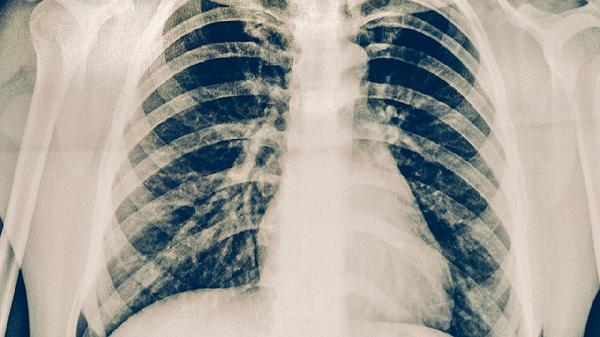

两肺下叶间质性改变通常指肺部间质组织出现异常,可能由慢性炎症、尘肺病、结缔组织病、药物反应或特发性肺纤维化等原因引起,需结合影像学与临床症状综合评估。

胺碘酮、甲氨蝶呤等药物可能诱发药物性肺损伤,CT显示两肺下叶磨玻璃影伴间质增厚。及时停药并应用抗氧化剂可改善病变,严重时需进行氧疗支持。

不明原因的进行性肺纤维化多见于中老年人,典型表现为双下肺蜂窝状改变和Velcro啰音。吡非尼酮、尼达尼布等抗纤维化药物可延缓病程,晚期需考虑肺移植。

确诊需完善高分辨率CT、肺功能及血清学检查。日常应避免吸烟及二手烟暴露,保持适度有氧运动如快走、游泳以增强肺功能。饮食推荐高蛋白、富含维生素C/E的食物如鱼类、坚果、柑橘类水果,有助于减轻氧化应激。冬季注意防寒保暖,定期监测血氧饱和度,出现呼吸困难加重需立即就医。